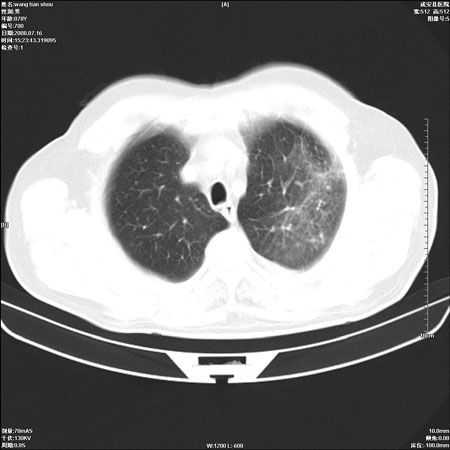

以下是引用qingjing在2008-7-16 19:55:00的发言:[br]1、左上肺不张并堵塞性炎症,建议支气管镜详查;[br]2、左侧胸腔少量积液。

以下是引用wzr在2008-7-16 20:26:00的发言:[br]左肺肺不张伴阻塞性肺炎!另:左侧胸腔少量积液。建议纤支镜检查!